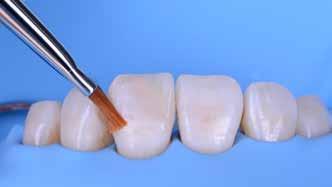

A módszer első lépéseként a gipszből kiöntött csonkokat platinafóliával borítjuk (5. ábra). Az adaptálását követően a felhelyezett fóliát óvatosan eltávolítjuk, felhevítjük, majd ismét visszahelyezzük a csonkokra. Ezt követően történik meg az első kerámiaréteg felvitele (Waschbrand). Az első égetés során csupán egy nagyon vékony réteg kerámia kerül a fólia felszínére (6. ábra). Amikor az égetést követően ezt

a kezdetleges kerámiavázat visszahelyezzük a csonkokra, a kerámia anyagában vékony repedések alakulnak ki. A végleges restaurátum elkészítéséhez szükséges kerámia „köpeny” ekkor áll készen a további kerámiarétegek felvitelére és kiégetésére (opaker réteg, dentin- és zománcmassza felvitele) (7-10. ábra). A készülő fogpótlás végső formai megjelenése rétegenként kerül kialakításra.